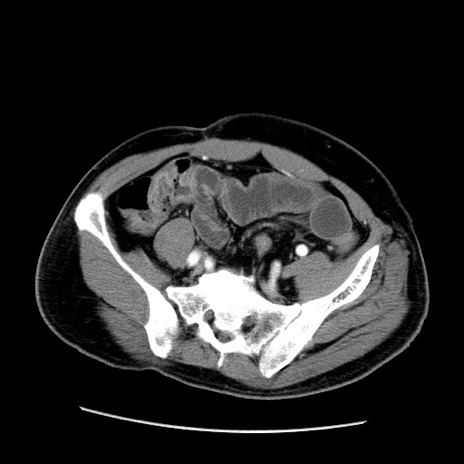

症例22(横断像)

【症例】50歳代男性

【主訴】腹痛

【現病歴】AVMからの被殻出血のため回復期リハ病棟入院中。 本日午後3時頃急に下腹部痛が出現した。

【既往歴】AVM、被殻出血、虫垂炎、高血圧

【身体所見】意識晴明、左半身不全麻痺、会話の理解は良好、36.5°C、腹部:膨隆、全体に板状硬、下腹部正中に圧痛点あり、反跳痛-、筋性防御不明、右下腹部にope scar

【データ】WBC 9400、CRP 0.06